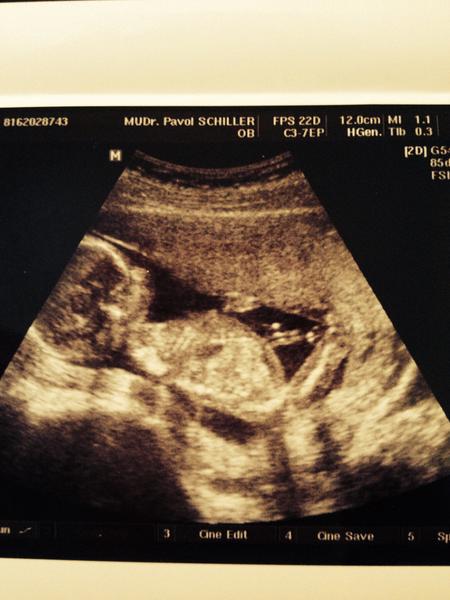

@miscok ahojky, jezis malinke je krasne 🙂...aky uzasny cloviecik 🙂....a chodis k Schillerovi? ja som u neho bola parkrat v Malackach este...mne sa velmi pozdaval 🙂...a kde je teraz?...